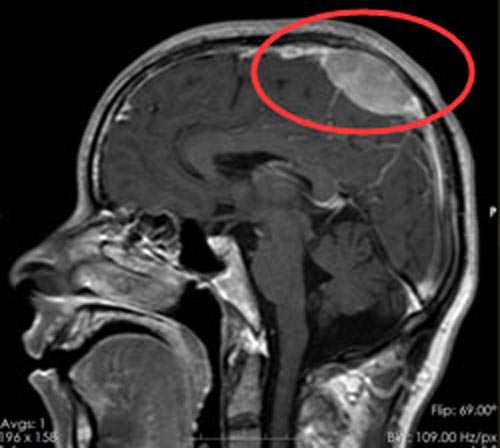

43岁的文先生素来身体强健,二天前在没有任何诱因的情况下突然倒地,四肢抽搐,家人急忙大声的呼唤他,这时的文先生已呼之不应,持续数分钟清醒,之后,文先生不能回忆当时的情景。全家人刚刚从恐慌中逐渐平静下来的时候,第二天文先生再次出现突然倒地、四肢抽搐。一家人不敢再大意,赶紧送他到当地医院就诊,头颅CT检查提示:左侧顶部大脑镰占位。

在广东三九脑科医院综合神经外科进行了进一步检查,医生告诉他的家人:文先生有手术指征,该部位肿瘤的一个重要的临床症状就是癫痫发作,多以对侧肢体或面部局限性发作开始,逐渐形成全身大发作。

完善术前准备后,外五科医生团队在全麻下为文先生行“左侧顶部大脑镰窦脑膜瘤切除术+上矢状窦重建术”,术中采用导航定位,剪开硬脑膜,肿瘤与硬膜粘连,质中偏硬,血运丰富,广基与大脑镰相连,大小约4.0cm×5.5cm×3.5cm,完全切除肿瘤,手术顺利,未予输血,术后给予脱水、改善微循环等对症治疗。